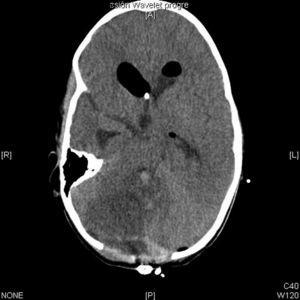

La tomografía computarizada (TC) cerebral con contraste mostraba una tumoración en el techo del cuarto ventrículo con calcificaciones, edema perilesional e hidrocefalia triventricular (fig. 1). Las resonancias magnéticas (RM) cerebral y de neuroeje con gadolinio confirma la presencia de la tumoración con una alta sospecha de ependimoma (fig. 2).

Figura 1.TC craneal con contraste al diagnóstico. Tumoración en el techo del cuarto ventrículo con calcificaciones, edema perilesional e hidrocefalia triventricular.